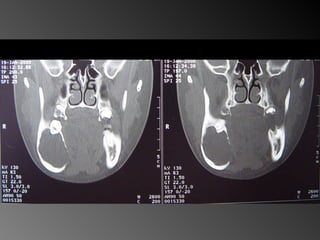

26 - Paciente do sexo feminino, 30 anos de idade, se apresentou com aumento de volume no corpo da mandíbula, região dos dentes 45, 46 e 47, assintomático e com evolução de aproximadamente 1 ano. Pelo exame clínico constatamos expansão óssea e deslocamento dos dentes 45 e 46 de suas posições normais. Através de radiografia panorâmica observamos uma imagem radiográfica multilocular onde as trabéculas ósseas se encontravam perpendicularmente umas às outras e em outras regiões com aspecto de bolha de sabão. Com base no quadro clínico, o diagnóstico é: a) Ceratocisto e mixoma odontogênico. b) Odontoma composto e ameloblastoma. c) Mixoma odontogênico e ameloblastoma. d) Mixoma odontogênico e odontoma composto. e) Ameloblastoma e ceratocisto.

26 - Pacientedo sexo feminino, 30 anos de idade, se apresentou com aumento de volume no corpo da mandíbula, região dos dentes 45, 46 e 47, assintomático e com evolução de aproximadamente 1 ano. Pelo exame clínico constatamos expansão óssea e deslocamento dos dentes 45 e 46 de suas posições normais. Através de radiografia panorâmica observamos uma imagem radiográfica multilocular onde as trabéculas ósseas se encontravam perpendicularmente umas às outras e em outras regiões com aspecto de bolha de sabão. Com base no quadro clínico, o diagnóstico é: a) Ceratocisto e mixoma odontogênico. b) Odontoma composto e ameloblastoma. c) Mixoma odontogênico e ameloblastoma. d) Mixoma odontogênico e odontoma composto. e) Ameloblastoma e ceratocisto.

Ameloblastoma Freqüência: -1% de todos os cistos e tumores dos maxilares - Maior ocorrência entre a segunda e a quinta décadas de  Vida (picos entre 35 e 45)  -80% ocorrem na mandíbula -Área de molares inferiores, ramo ascendente de  mandíbula.  -Na maxila: molares superiores, seios maxilares e assoalho  da fossa nasal  (TOMMASI e FERNANDES, 2002)

Mixoma Freqüência:  -Segunda e terceira década de vida -Atinge pouco mais a maxila que a mandíbula (região posterior + frequente)

Ameloblastoma Freqüência: -1%de todos os cistos e tumores dos maxilares - Maior ocorrência entre a segunda e a quinta décadas de Vida (picos entre 35 e 45) -80% ocorrem na mandíbula -Área de molares inferiores, ramo ascendente de mandíbula. -Na maxila: molares superiores, seios maxilares e assoalho da fossa nasal (TOMMASI e FERNANDES, 2002)